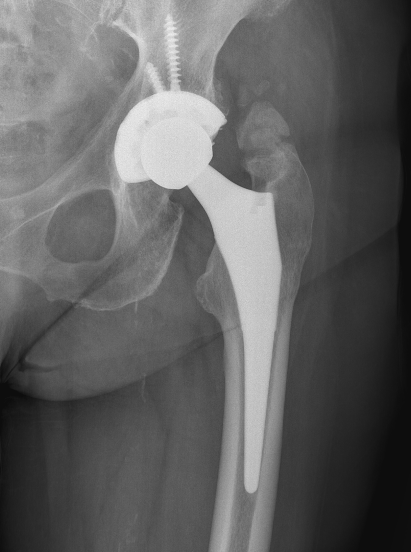

Brooker Classification: Type III and Type IV clinically relevant

Type I: Isolated islands of bone

Type II: Bony spurs from pelvis and proximal femur, gap > 1 cm

Type III: Gap < 1 cm

Type IV: Apparent ankylosis